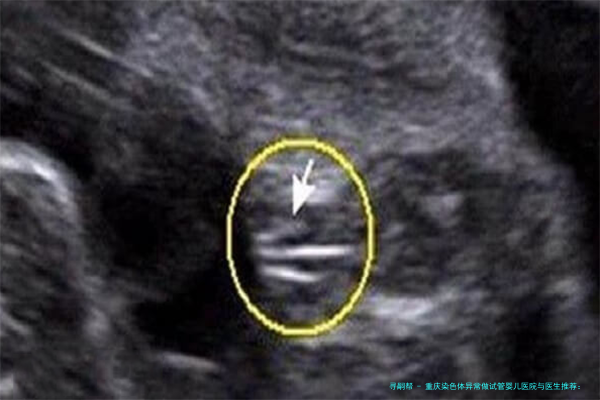

染色体异常是导致胚胎停育、复发性流产或出生缺陷的重要缘由之一。传统的试管婴儿技术(、二代)主要解决的是精卵结合和受精的问题,而第三代试管婴儿(PGT) 的核心在于胚胎移植前的遗传学检测。它可以在胚胎移植前,对胚胎的染色体进行筛选,抉择染色体正常的健康胚胎进行移植,从而显著提高妊娠,降低小产风险,阻断遗传性疾病。这就像在播种前对种子进行1次“优先选择”,确保其健康无虞。